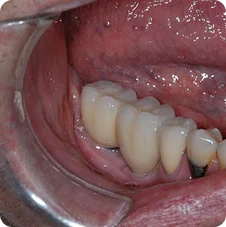

Pre-operative